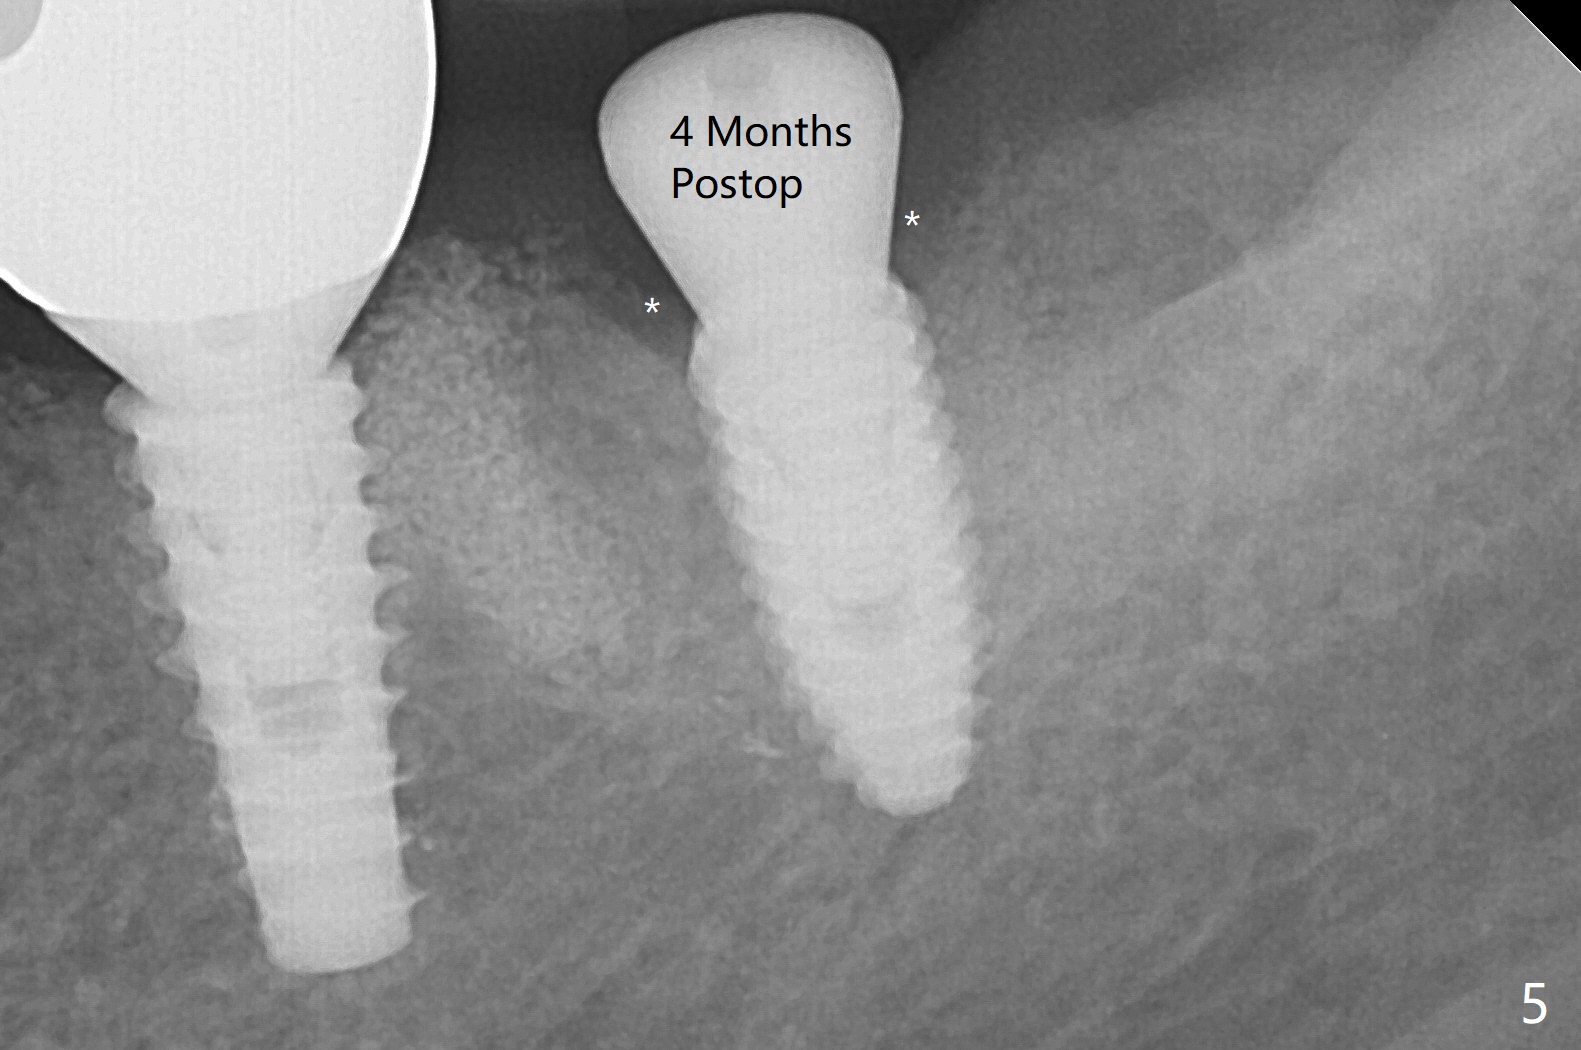

A 55-year-old woman is going to have implant placement at #18 using surgical guide 5 months post socket preservation (Fig.1). The bone density of initial osteotomy until 3.5x7.3 mm drill seems to be soft (Fig.1,2). Underprep is decided for the remaining osteotomy (Fig.3). The last drill is 3.5x10 for 4.5x10 mm implant (Fig.4). In fact initial insertion torque is >55 Ncm. The implant has to be backed up several times to get final torque ~ 35 Ncm. Retrospectively the bone density of the lower portion of the osteotomy is higher than that of the upper one (compare Fig.2,3). There is crestal bone (grafted one *) resorption 4 months postop (Fig.5).